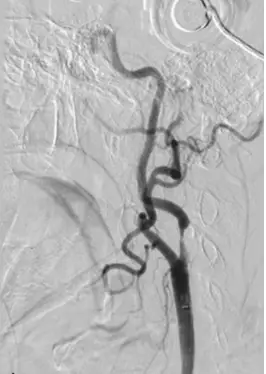

影像為選擇性 common carotid artery 數位減影血管攝影。可見:

- 自下而上之粗大暗影為 common carotid artery (CCA)。

- 於頸動脈分叉後,前方較細、分支眾多者為 external carotid artery (ECA),其管腔通暢。

- 後方向顱側走行之血管呈「細線樣 (string sign)」並於遠端再度擴張,顯示 ICA 起始段幾近完全閉塞的高級狹窄。(pubs.rsna.org)

因此病灶位於 ICA 而非 ECA。